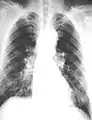

تبقى أشعة الصدر غير الطبيعية وتفسيرها أهم العوامل في إثبات وجود التليف الرئوي.[10] تظهر النتائج عادة على شكل عتمات متنيّة صغيرة غير منتظمة في الجزء السفلي للرئة. يُستحدم نظام تصنيف منظمة العمل الدولية، "s" ، "t"، و / أو "u" عتامة الغلبة. يُعتبر التصوير المقطعي المحوسب أو التصوير المقطعي المحوسب عالي الدقة أكثر حساسية من التصوير الاشعاعي العادي في الكشف عن التليف الرئوي (وكذلك أي تغييرات كامنة في الغشاء البلوري). يعاني أكثر من 50 ٪ من المصابين بالتليف الرئوي من وجود تكتلات للأسبست في الغشاء الجداري البلوري، وانكماش المسافة بين جدار الصدر والرئتين. وبمجرد ظهور تلك التكتلات، قد تتطور النتائج الإشعاعية في الأسبست ببطء أو تظل ساكنة، حتى في غياب المزيد من التعرض لمادة الأسبست.[18]

رئة ذات 61 سنة لشخص يعمل في صناعة الأسبست لعقود.